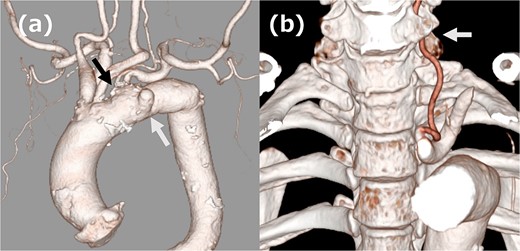

A 68-year-old male patient had undergone distal aortic arch replacement with lateral thoracotomy 13 years earlier for chronic distal aortic arch dilatation of a type B aortic dissection of unknown onset. Three years ago, a saccular aortic aneurysm, probably arising from the anastomosis site, was observed; as it had a tendency to dilate over time, surgical intervention to prevent rupture was decided upon. Although the patient was scheduled for TEVAR, his anatomy showed an ILVA with its origin in a position of forced occlusion due to the stent graft landing in zone 2 (Fig. 1a). In most cases, the entry of the ILVA under the transverse process of the vertebra is at the fifth cervical vertebra; however, in this case, the entry was from the sixth cervical vertebra (Fig. 1b). Magnetic resonance angiography showed poor delineation of the bilateral posterior communicating arteries, and the Willis arterial circle was likely nonfunctional, suggesting that revascularization of the ILVA would be beneficial for neurological prognosis (Fig. 2).

(a) Three-dimensional computed tomography (3DCT) image. The white arrow indicates the aortic aneurysm, and the black arrow indicates ILVA. (b) 3DCT image. The white arrow indicates the entry of ILVA under the transverse process of the vertebra at the sixth cervical vertebra.